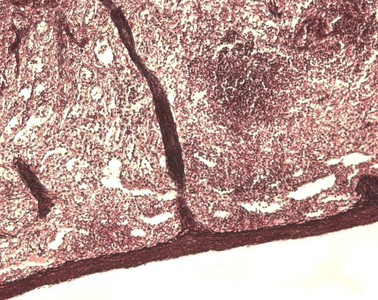

Präparat 34: Milz, Versilberung und Kernfärbung

Intensiv gefärbtes (hohe Zelldichte) Organ, durch eine Kapsel scharf von der Umgebung abgegrenzt. Im Inneren sind dunkle, rundliche Gebilde (Malpighi-Körperchen = Milzknötchen) zu erkennen, weiter große Gefäßanschnitte und Bindegewebstrabekel, die von der Kapsel ausgehend das Innere des Organs durchziehen. Am Hilum des Organs sieht man anhängende Reste von Fett und Bindegewebe, darin Gefäßanschnitte.

Milzknötchen

Organkapsel

bindegewebige Kapsel mit elastischen Fasernetzen und Kollagenfasern, die einem Organ in seiner Umgebung den nötigen Halt gibt.